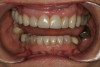

Fig 6. Deep bite, excessive wear, and missing No. 9 present a challenging case for restorative rehabilitation.

Figure 6